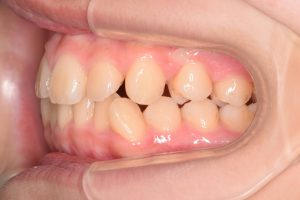

左側

0000000004

0000000025

0000000076

1期治療開始時(2024年3月)

2期治療開始時(2024年11月)

保定開始時(2025年1月)の写真です。